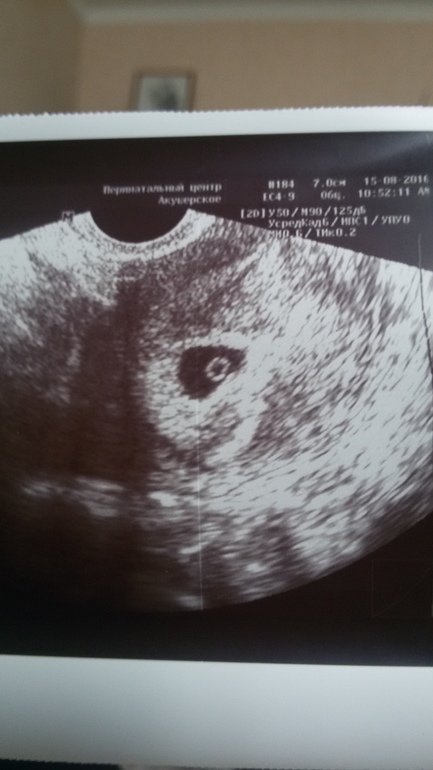

Привет девочки помогите мне успокоится, у меня М были последние 26.06 получается сейчас 7 недель и 1 день , О не отслеживала, была сегодня на Узи плодное яйцо есть , а эмбриона нет и сердечко не слышно , моя Г говорит что это плохо , в пятницу на прием еще раз , может ли мое чудо просто быть на 6 неделе? ??

это сегодня

Да 30,07😆 ктр 1.3 мм, желточный мешок 3.2мм , диаметр яйца плодного 13.8 мм

Ну вон, желточный мешочек то появился на втором снимке его видно, значит скоро и лялика своего увидите.